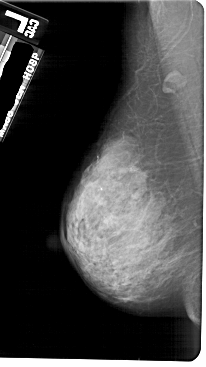

A_1753_1.LEFT_MLO

LEFT_MLO LINES 5491 PIXELS_PER_LINE 3076 BITS_PER_PIXEL 12 RESOLUTION 43.5 NON_OVERLAY